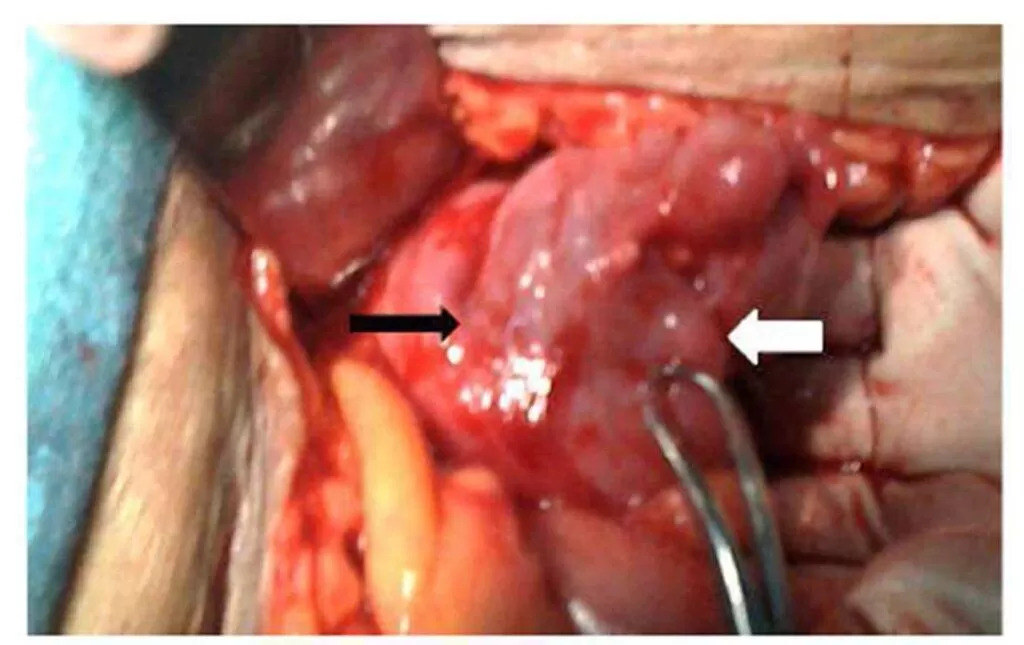

Exploratory laparotomy was performed and the sigmoid colon was found adherent to the anterior wall of the uterus (Fig.4).

Figure 4:  Sigmoid colon (black arrow) adherent to anterior surface of the uterus (white arrow).

Their separation demonstrated the fistulous opening in the sigmoid colon (Fig.5).The tract was excised along with resection of a small segment of sigmoid colon because of inflammation and scarring, and the continuity of the colon was restored. The internal os was dilated with Hegar dilator under visual guidance to relieve the cervical stenosis. The uterine wound was closed, and bilateral tubal ligation was performed. The post-operative period was uneventful and the patient has normal menses since then. The resected specimen of bowel sent for histopathology revealed the presence of tubercular disease.